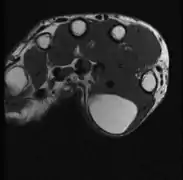

A physical exam is typically the easiest way to diagnose it. Rarely, a tissue biopsy or imaging may be required. The imaging modality of choice is magnetic resonance imaging (MRI), because it has superior sensitivity of distinguishing it from liposarcoma as well as mapping the surrounding anatomy.[20]

Medical ultrasonography of a lipoma in the thenar eminence: It is hyperechoic compared to adjacent muscle, and relatively well-defined, with miniature hyperechoic lines.[21]

MRI showing lipoma of the arm